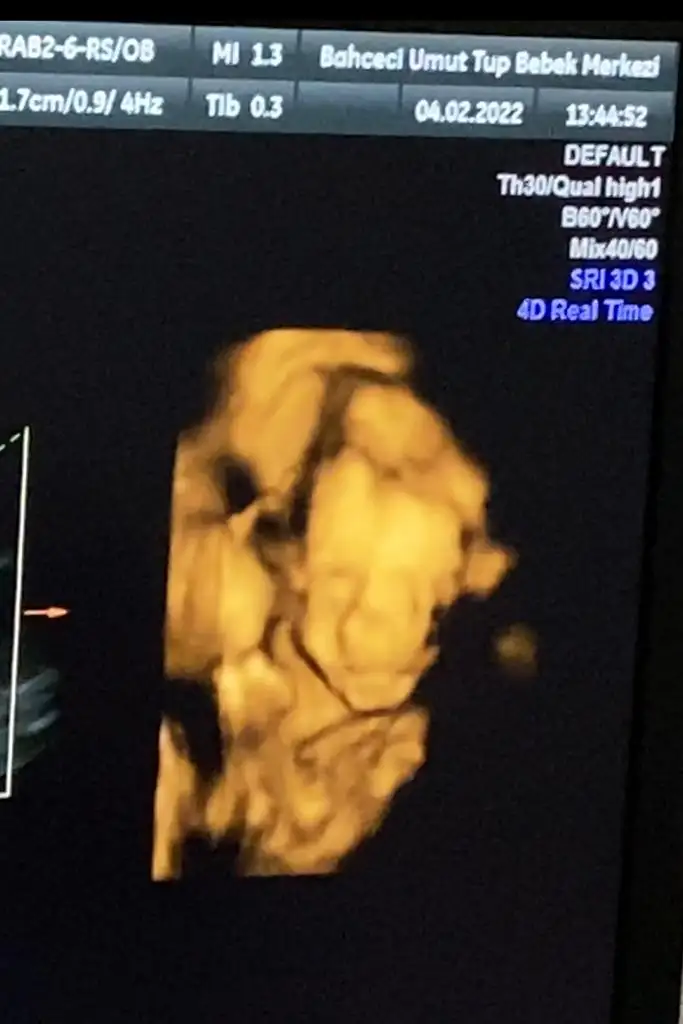

her şey yolunda dedi638 gram olmuş minik tırtıl

rahim ağzı uzunluğunu ölçtü 48 milim dedi, iyiymiş,

uyuyodu minik tırtıl ama uykusunda da hareketliydi gülüyodu, bi şeyler yapıyodu

fotosunu da bırakayım günümüz şenlensin mi